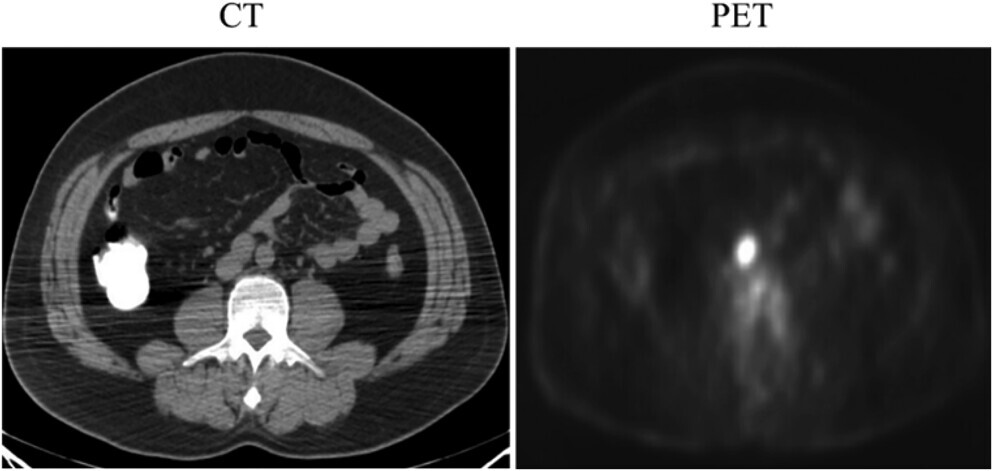

КТ-сканирование, показывающее один увеличенный забрюшинный лимфатический узел у больного семиномой, и соответствующее позитронно-эмиссионное томографическое (ПЭТ) сканирование, показывающее усиление сигнала. Патоморфологическое заключение соответствовало метастатической семиноме.